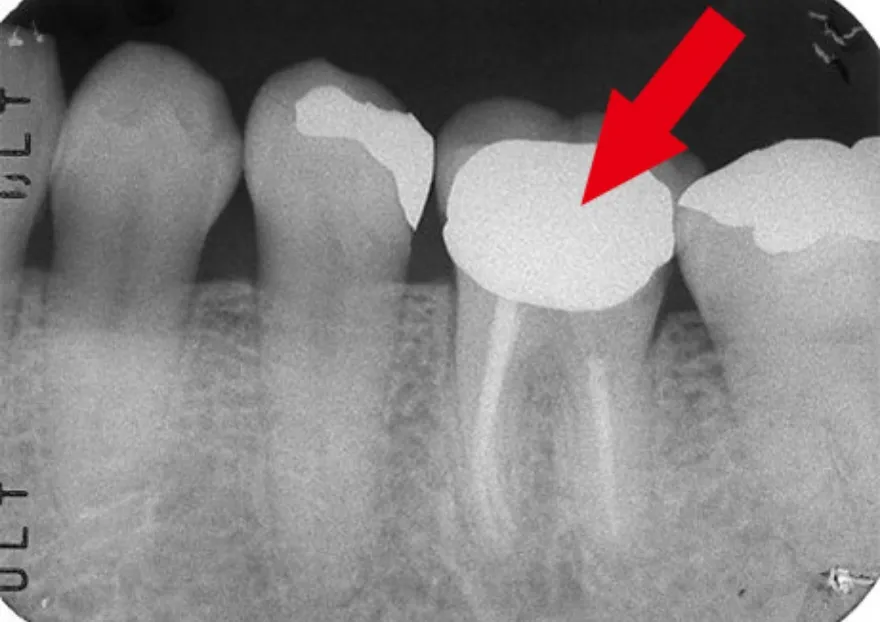

エックス線写真でみる根管治療

• 根管治療前のエックス線写真では、根の先端から股の部分にかけて黒い影が見えます。これが根尖病巣です。

• 根管治療後のエックス線写真では、根の中に詰めた薬剤が白く映っています。根の周りにあった黒い影が消えているのが分かります。